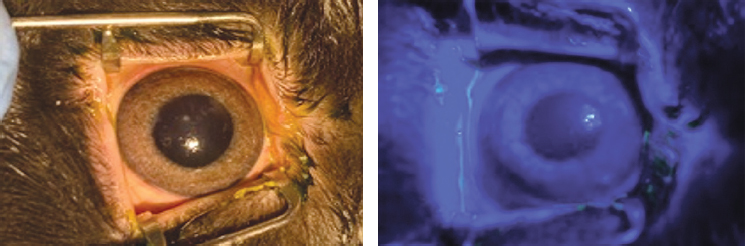

По данным биомикроскопической картины глазной поверхности во всех группах на 1-е сутки эксперимента отмечали равномерное глубокое помутнение стромы роговицы за счёт её отёка — 4,00 [4, 00; 4, 00] баллов (p > 0,05), деэпителизацию с прокрашиванием раствором флуоресцеина натрия — 100,00 [100, 00; 100, 00] % (p > 0,05), а также отсутствие новообразованных сосудов — 0 баллов (рис. 1–3).

Рис. 1. Биомикроскопическая картина роговицы у животных 1-й группы на 30-е сутки: отсутствие помутнения, новообразованных сосудов, роговица полностью эпителизирована / Fig. 1. Biomicroscopic picture of the cornea in animals of the 1st group, Day 30: no clouding, no new vessels, a complete epithelialization of the cornea

Рис. 2. Биомикроскопическая картина роговицы у животных 2-й группы на 30-е сутки: отсутствие помутнения, новообразованных сосудов, роговица полностью эпителизирована / Fig. 2. Biomicroscopic picture of the cornea in animals of the 2nd group, Day 30: no clouding, no new vessels, a complete epithelialization of the cornea

Рис. 3. Биомикроскопическая картина роговицы у животных 3-й группы на 30-е сутки: помутнение в оптической области, наличие новообразованных сосудов до места дефекта эпителия, эрозия роговицы / Fig. 3. Biomicroscopic picture of the cornea in animals of the 3rd group, Day 30: no corneal clouding in optical zone, neovascularization over the whole cornea, corneal erosion